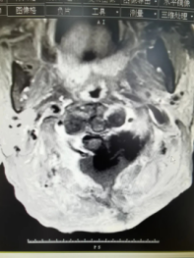

术前 术后

术前术后的影像图片对照

本次手术病人的肿瘤位于颅颈交界处,手术风险相对较高,稍有不慎就可能导致脊髓和血管的损伤,引起严重后果。患者赖婆婆已经出现严重的神经压迫症状,手术是唯一办法。术前通过充分评估,患者虽然已82岁高龄,但身体机能还比较好,手术成功率高。在市人医神经外科、麻醉科、影像科等多学科配合的前提下,最大限度保证了患者的医疗安全。为赖婆婆实施的“颈椎管肿瘤切除术”,整个过程只用了一个多小时,术中严格控制出血和减少创伤,全切肿瘤,且神经血管保护良好,手术过程顺利,术后患者情况稳定,神经症状明显缓解,术后一周康复出院。